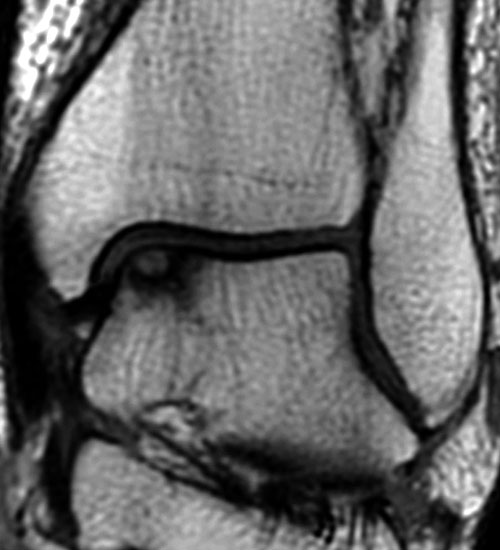

Die Standardsequenzen umfassen Fast-Spin-Echo (FSE) und Gradientenechosequenzen 22. Die Pulssequenzen umfassen typischerweise Protonendichte (PD) und fettunterdrückte Protonendichte Sequenzen (PD-FS) 17. In unserem eigenen Protokoll verwenden wir aktuell isotrope 3D-Gradientenechosequenzen (true FISP) (Abb. 3), protonendichte-fettunterdrückten Turbo-Spin-Echo-Sequenzen (PD-FS-TSE) (Abb. 4 und 5) und T1-gewichtete Spinechosequenzen (Abb. 6). Wichtig ist letztendlich die räumliche Auflösung als Funktion der Schichtdicke, dem Blickfeld (FOV) und der Bildmatrix 17.